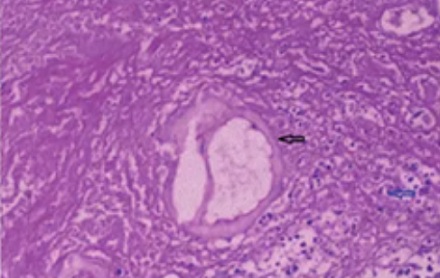

包虫的成虫生活在狗的肠道里,在 30 厘米长的狗小肠内,成虫的寄生数量可高达 3 万余条,每日可排出约 10 万个虫卵。——数据来源:《甘孜日报》